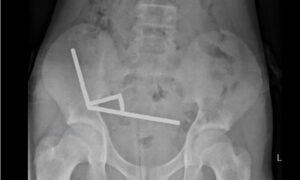

যেখানে ডাক্তাররা পেটের ভেতর চুম্বক আবিষ্কার করেন। চুম্বকগুলো একসঙ্গে সংযুক্ত হয়ে তার অন্ত্রের ভিতরে চারটি শিকল তৈরি করেছিল।

হাসপাতালে পেট ব্যথা নিয়ে ভর্তি হওয়ার এক সপ্তাহ আগে প্রায় ৮০-১০০টি ৫x২ মিমি উচ্চ ক্ষমতাসম্পন্ন ‘নিওডিয়ামিয়াম চুম্বক’ গিলে ফেলেছিল ওই কিশোর। আট দিন হাসপাতালে থাকার পর তাকে ছেড়ে দেওয়া হয়েছে।